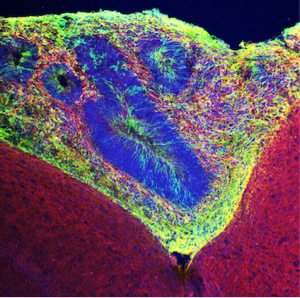

Gage’s team used human pluripotent stem cells to develop brain organoids, which were grown in culture for 40 to 50 days. Then, the team inserted the organoids into cavities made in mice’s retrosplenial cortex—a region critical for movement and spatial learning. The mice had “humanized” immune systems, Gage says, meaning that their immune cells had been engineered not to attack human tissue.

Around day 5 after transplantation, blood vessels in the organoids could be detected using a fluorescent dye, and by day 14 an extensive network of vessels had grown deep within the human tissue graft.

Within two to 12 weeks, the organoids were sprouting additional neurons, including ones found in very specific regions of the human cortex; glia cells including astrocytes; and neural stem cells. By 14 days almost all the organoids had developed a rich network of blood vessels carrying nutrients and oxygen, allowing them to survive for up to 233 days. Their structure and cell maturation was that of a newborn.